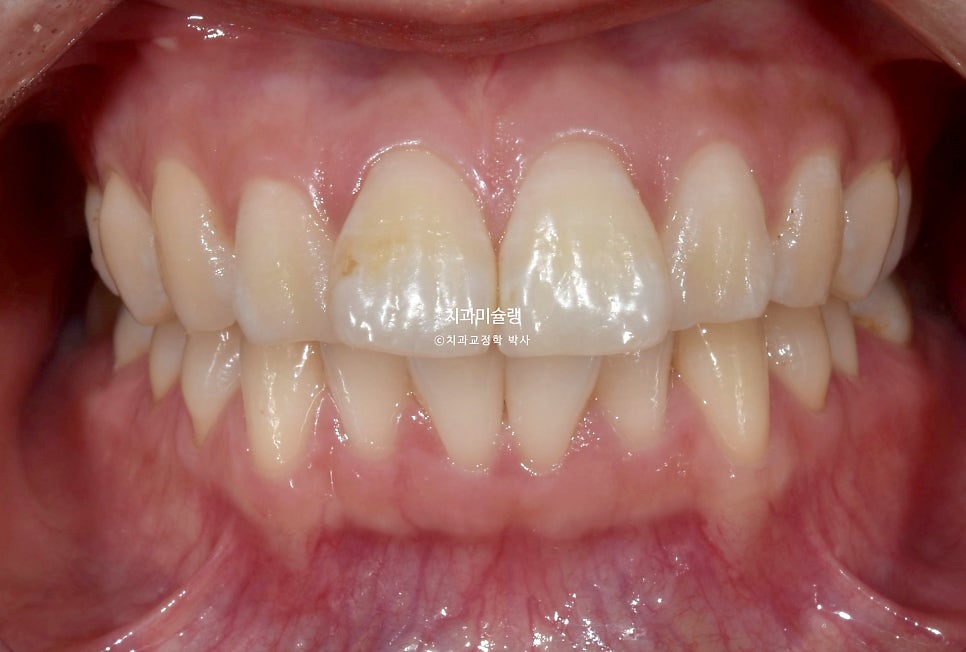

초진 시 구강 상태

앞니 돌출 때문에 입이 편하게 안다물어지는 입술부전증이 경미하게 있습니다.

입안을 보면 앞니가 뻗쳐있는 전형적인 돌출 입니다.

위아래 둘다 중절치가 특히 돌출되어 있습니다.